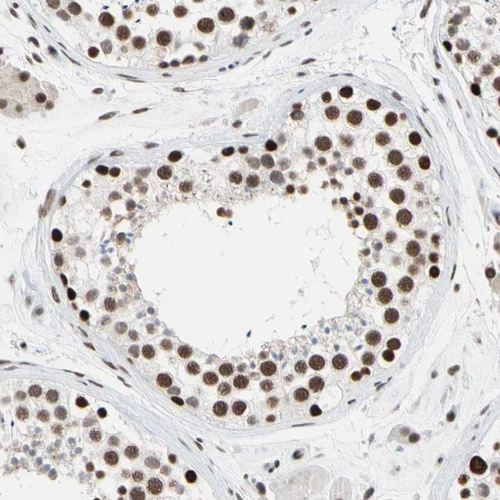

Immunohistochemical staining of human cerebral cortex, gastrointestinal, skeletal muscle and testis using Anti-FAM98B antibody HPA008502 (A) shows similar protein distribution across tissues to independent antibody HPA008320 (B).